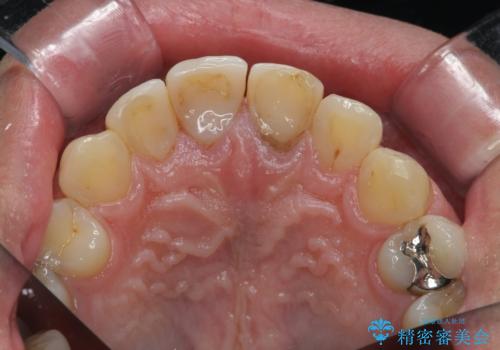

- 前歯の変色や形態を含む、見た目を改善したいと希望され来院されました。

視診・X線検査・歯周組織検査より下記のような問題が列挙され、長期的な予後を見込むために一つづつ問題の解決を計ります。

・不十分な根管治療 →マイクロスコープを用いる精密根管医療

・歯の変色 →ジルコニアクラウンの製作

・歯肉縁下カリエス →部分矯正による歯の挺出・歯周外科